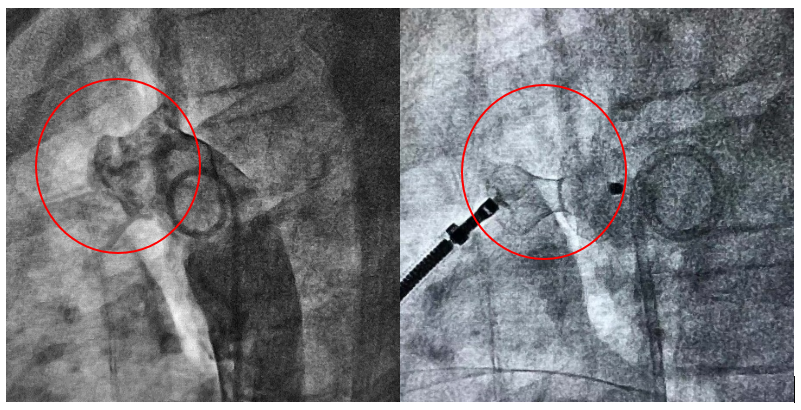

左图:主动脉造影可见主动脉和肺动脉间异常通道;右图:封堵器准确释放后PDA封闭

该患者是一名10岁儿童,因准备做耳鼻喉手术住院,术前准备过程中发现心脏杂音。通过超声心动图发现该儿童存在6mm动脉导管未闭(PDA)。长期动脉导管未闭导致大量持续性左向右分流,最终将导致肺动脉高压、心力衰竭等,甚至可能发生右向左分流、艾森曼格综合征,从而丧失手术机会死亡。及时闭合动脉导管,刻不容缓!心脏内科电生理团队在李学斌教授的指导下,经过周密的术前准备,儿科精心配合,优化手术流程,成功完成了PDA封堵术,以微创的手术治疗方式,使得困扰小朋友10年的先天性心脏病得到治愈。